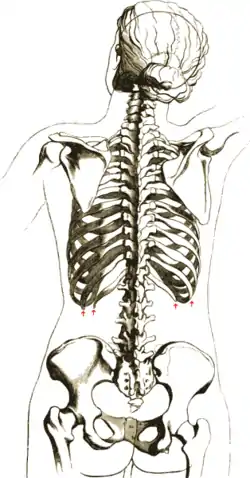

![]() The human rib cage. (Source: Gray's Anatomy of the Human Body, 20th ed. 1918.) | |

Thoracic Cage with Spine - Anatomy